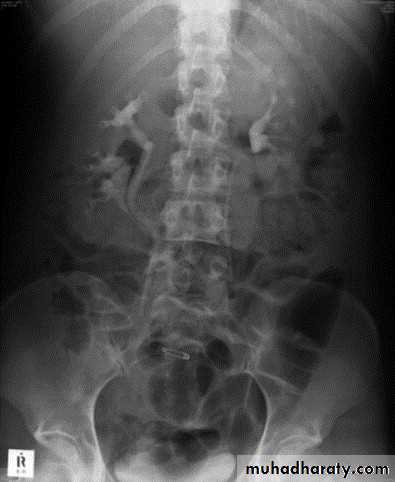

22- PUJ obstruction23- horse shoe24- PUJ obstruction25- double ureter26- partial PUJ obstruction27- double ureter28- schistosoma of bladder29- filling defect in the pelvi-calycial system30- tumor 31- filling defect (stone)